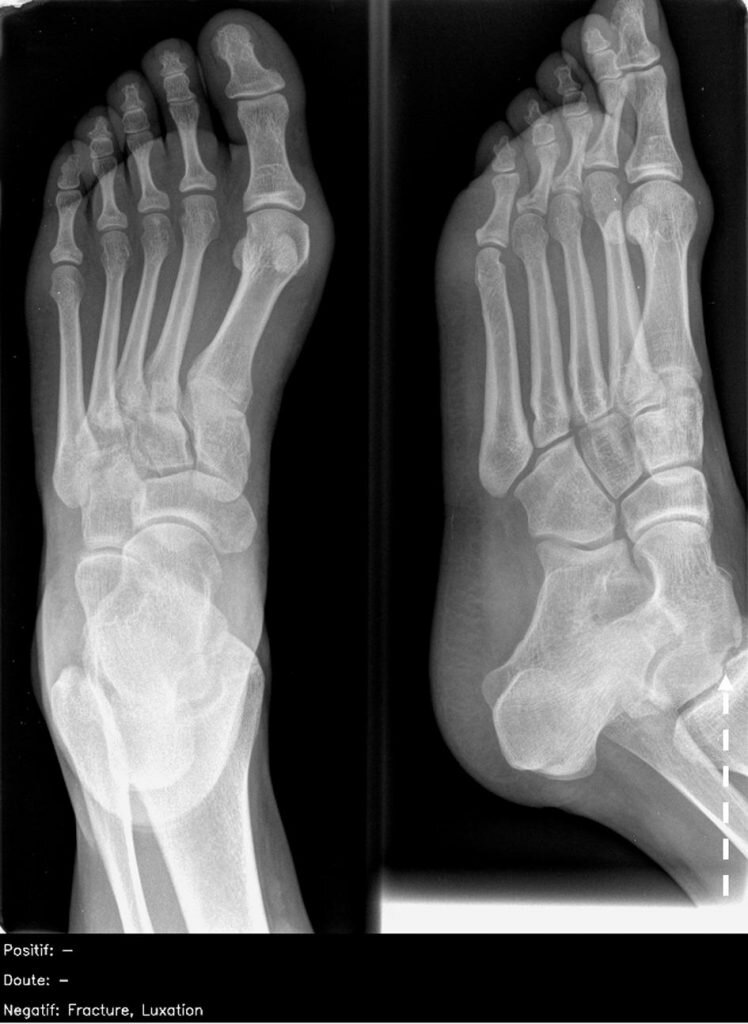

Примеры изображений из теста. Слева: нормальная рентгенограмма брюшной полости, на которой ИИ нашел правосторонний базальный пневмоторакс (ложно положительный результат). Справа: рентген стопы в двух проекциях, на котором виден костно-хрящевой дефект купола таранной кости (пунктирная линия), это нарушение пропустили все врачи и ИИ. Изображения: Susan Cheng Shelmerdine et al., BMJ